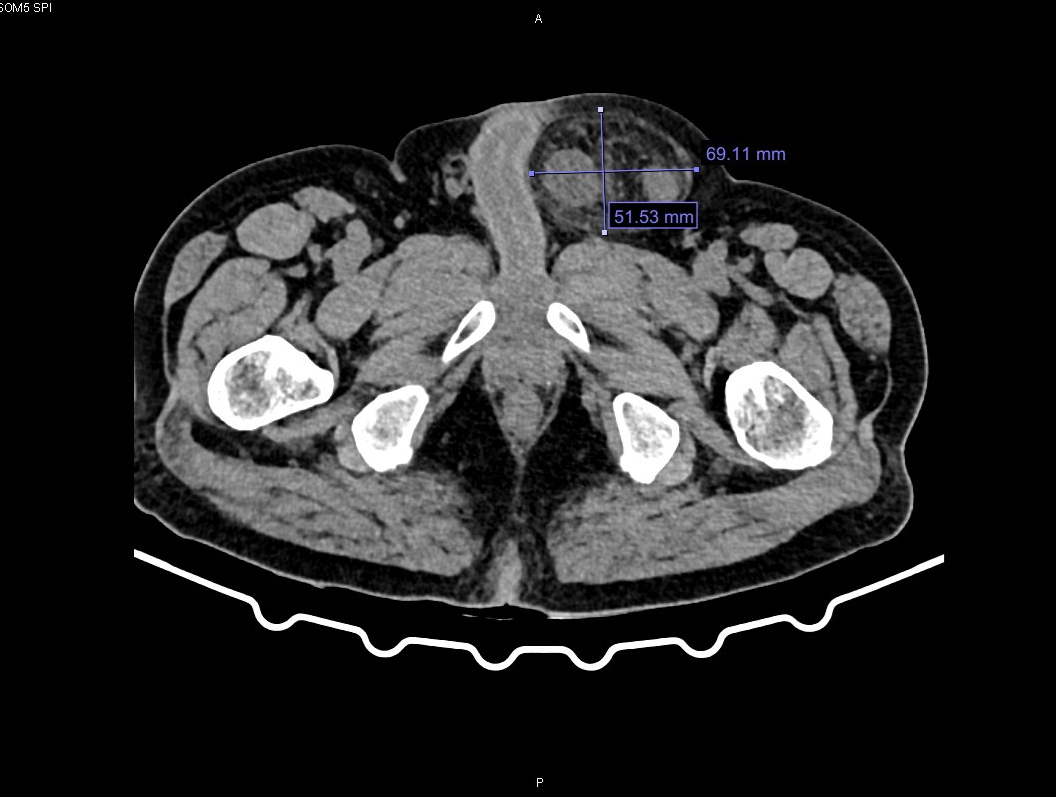

Trường hợp vừa được mổ cấp cứu là ông B.C.C (63 tuổi) trú tại phường Cẩm Phả, tỉnh Quảng Ninh. Bệnh nhân nhập viện trong tình trạng khối phồng vùng bẹn trái đau tức, không thể đẩy lên được kèm theo đau bụng và chướng hơi. Qua thăm khám và chụp cắt lớp vi tính, các bác sĩ chẩn đoán bệnh nhân bị thoát vị bẹn trái nghẹt. Hội chẩn đánh giá đây là biến chứng phức tạp và nguy hiểm của thoát vị bẹn do ruột bị chui xuống lỗ thoát vị và kẹt lại gây tắc nghẽn, thiếu máu nuôi. Bệnh nhân được chỉ định mổ cấp cứu bằng phương pháp nội soi, nhằm giải phóng khối thoát vị và xử trí tổn thương.

Hình ảnh khối thoát vị bẹn trái nghẹt qua phim chụp cắt lớp vi tính.